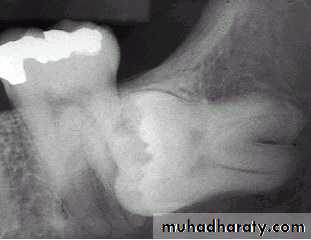

2 – prevention of Dental caries

Dental caries can occur at the lower 8 oradjacent lower 7 . most commonly at the

cervical line due to the inability of the patient

to clean the area thoroughly .